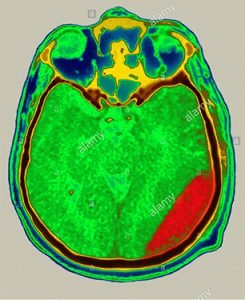

4. If brain CT scan is normal, he will be fine.

No, few times, delayed bleeding in the brain can occur. Small bleeding can be missed by CT or MRI scans.